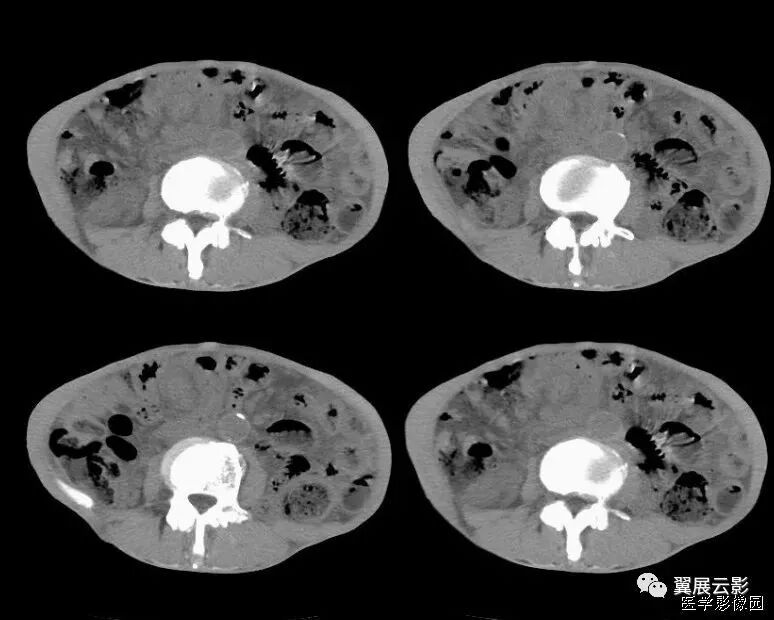

双环征

三环征